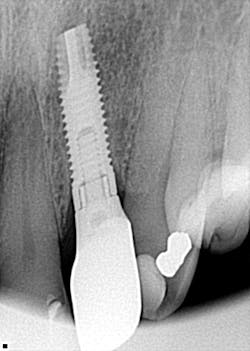

What implant is this?

So, here’s my challenge to you: Can you identify this implant (figure 7)?

Drop me an email at [email protected]!